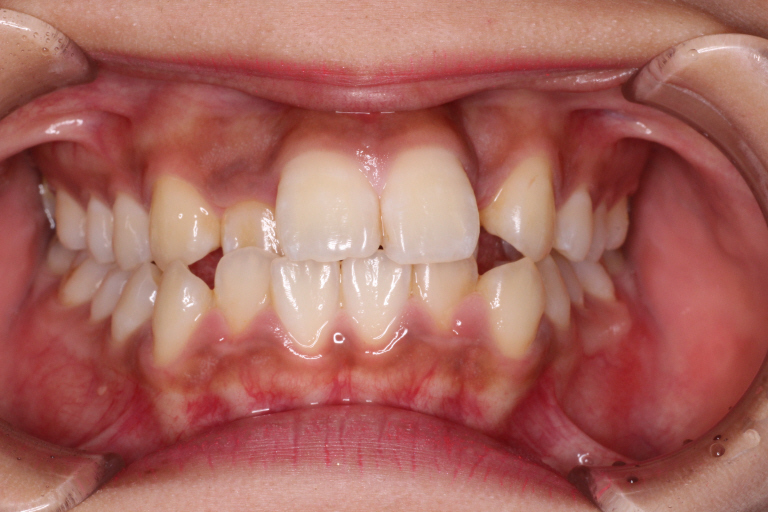

初診時のお口の中の状態です。

上の前から2番目の歯が下の歯列より内側にあり叢生です。

側方の上下の咬合関係が理想の上1本に対して下2本の理想的な噛み合わせではない。

歯列の幅がせまい。

診断:上顎前突・前歯部叢生